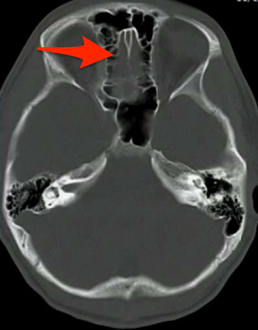

What is the most commonly injured cranial nerve in TBIs?

CN I. Patients will complain of things tasting weird because it controls 75% of taste.